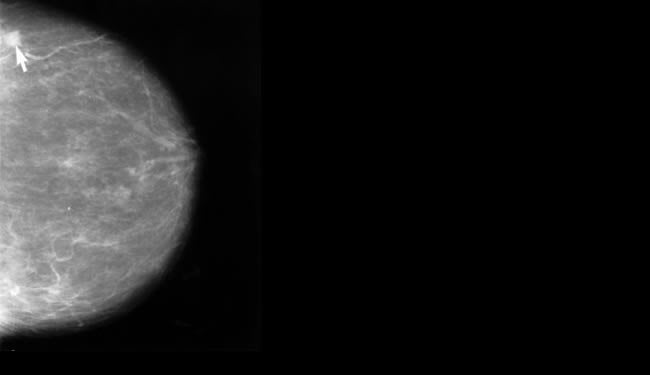

Breast Cancer Patients’ Brain Tissue Altered by Chemotherapy

Brain imaging studies of women with breast cancer before and after chemotherapy treatments show grey matter is being affected during the chemotherapy treatments. Brain areas believed to be critical for multi-tasking, memory and other cognitive functions were seen to change during the chemotherapy.